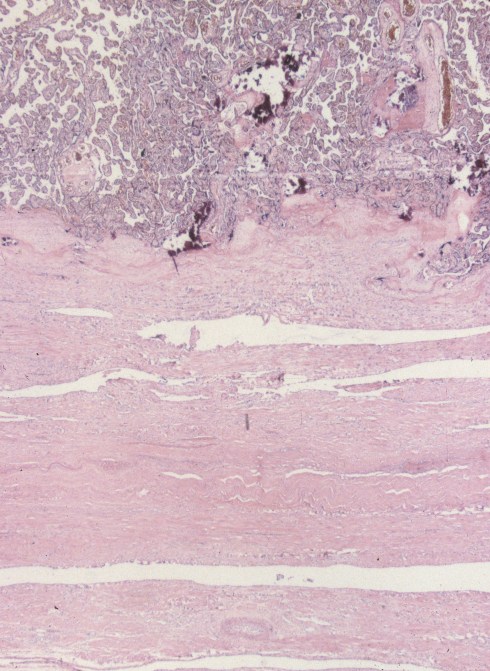

Fig 7a: This is a low magnification of the placenta on top with a thick chorionic base sitting over a relatively thin myometrium that ends at the serosa. This is from the same placenta as in Fig 5a-c. (H&E)

Fig 7b: The placenta in this image has a basal chorion implanted directly on a layer of serosa. This is the same placenta as in Fig 5d-e. (H&E, 20x)